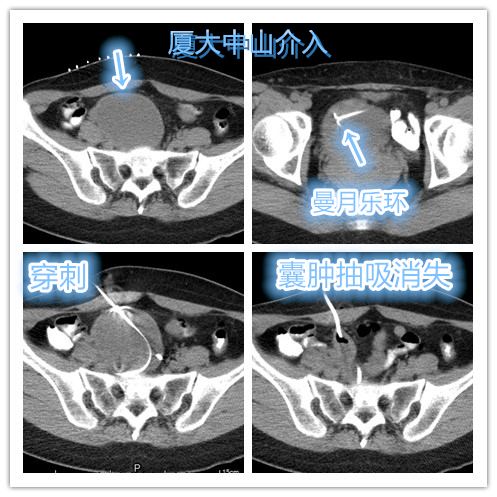

近期复查彩超提示双侧卵巢巧克力囊肿复发,右侧巧囊已经较大,担心再次破裂!但因恐惧再次腹腔镜手术治疗,辗转找到介入科,寻求介入穿刺硬化治疗。